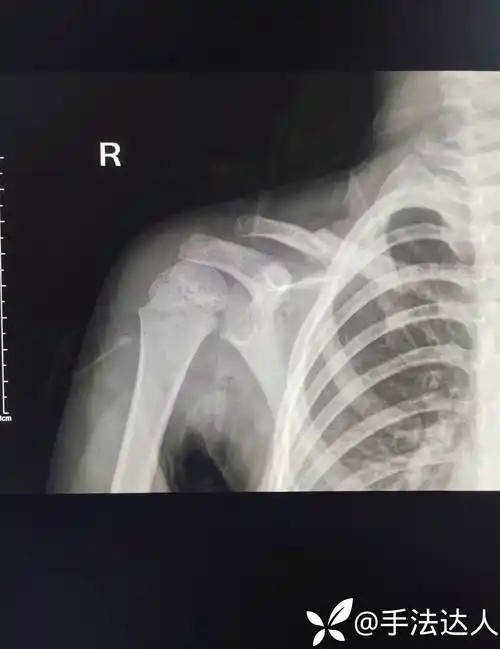

儿童锁骨骨折保守治疗(12岁以下)

右锁骨中段骨折

锁骨x光片